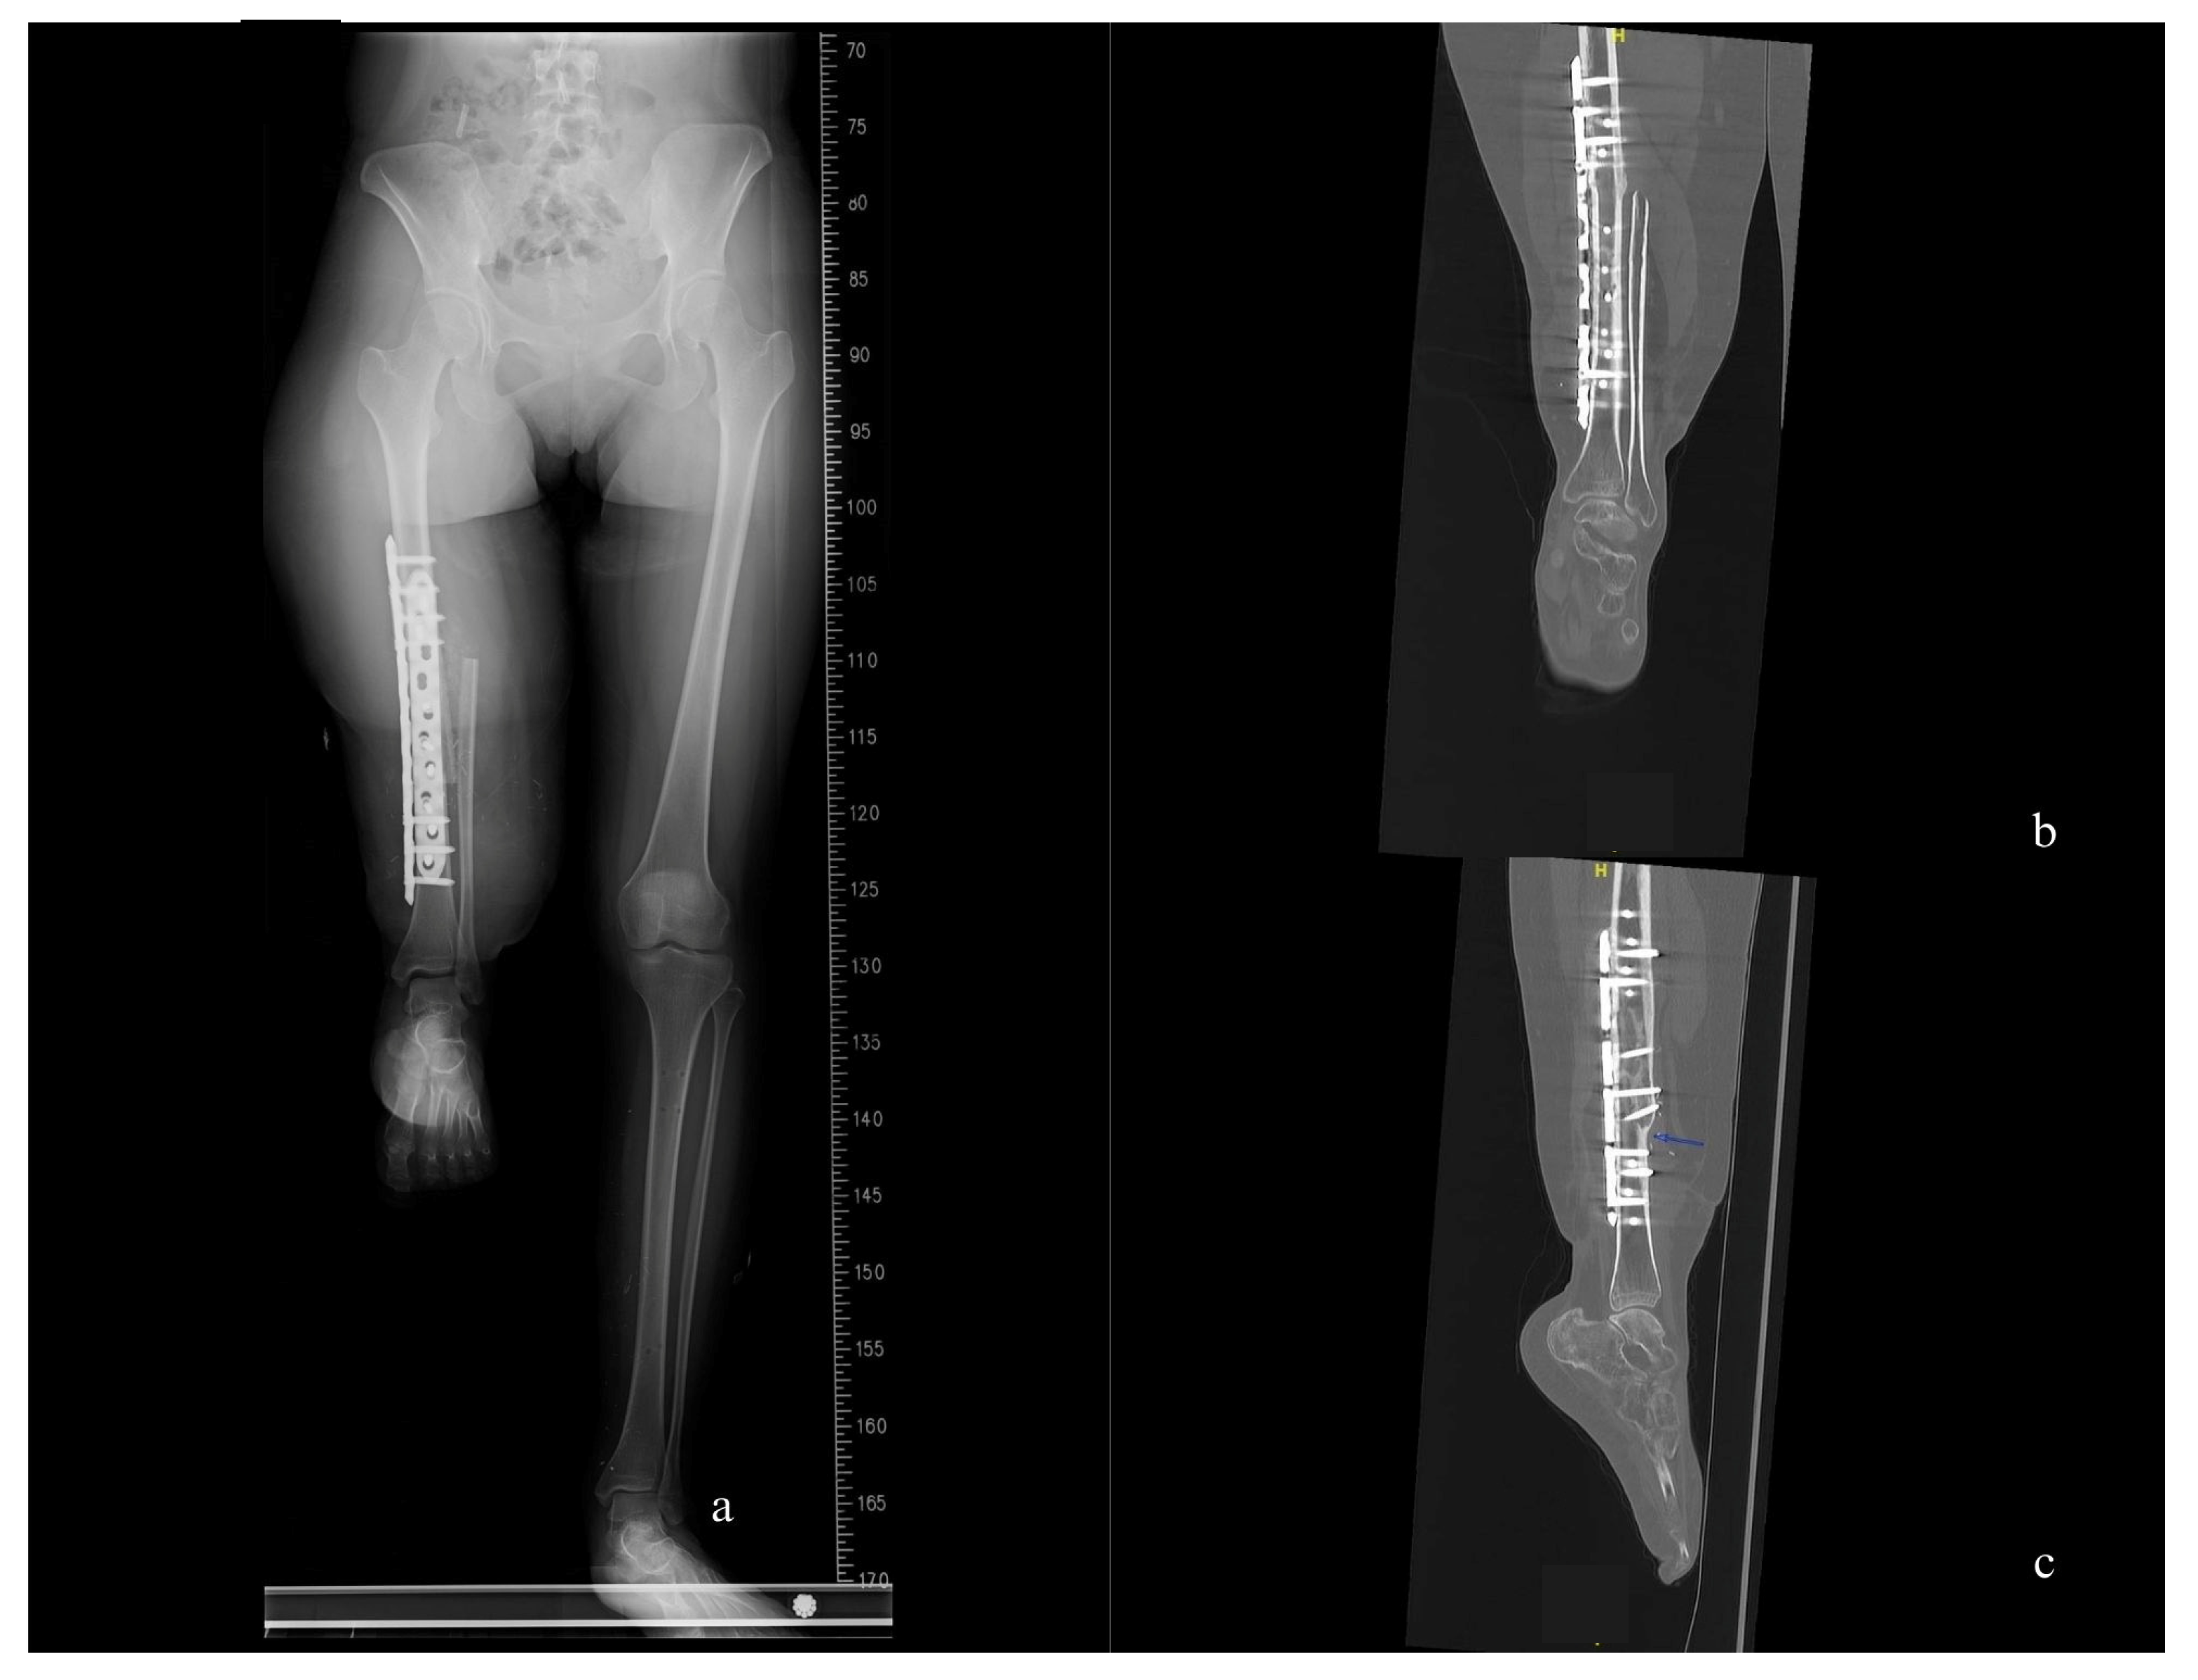

After two months, we conducted a follow-up X-ray of the surgical site, which revealed bone union and appropriate alignment of the leg axis. Five months after the rotationplasty, the patient demonstrated excellent ambulation and could independently climb stairs at the twelve-month follow-up (Figure 3 and Figure 4, and Supplementary Video S1, Figures S1 and S2). Regarding sensory recovery, the patient reported hypersensitivity and pain (visual analog score: 5) over the plantar area of the reversed knee at the two-month follow-up. However, sensation significantly improved without pain at the eighteen-month follow-up, with tactile sensation now present over the entire foot and ankle. The two-point discrimination test over the plantar and heel area measured 4 cm.

Figure 3. The position of the right “new knee” is appropriate. (a) Whole-leg axis radiographs at the two-months follow-up. (b,c) CT scans were conducted at the twelve-month follow-up, revealing complete healing of the bone union site and a straight alignment of the leg axis in coronal and sagittal view.